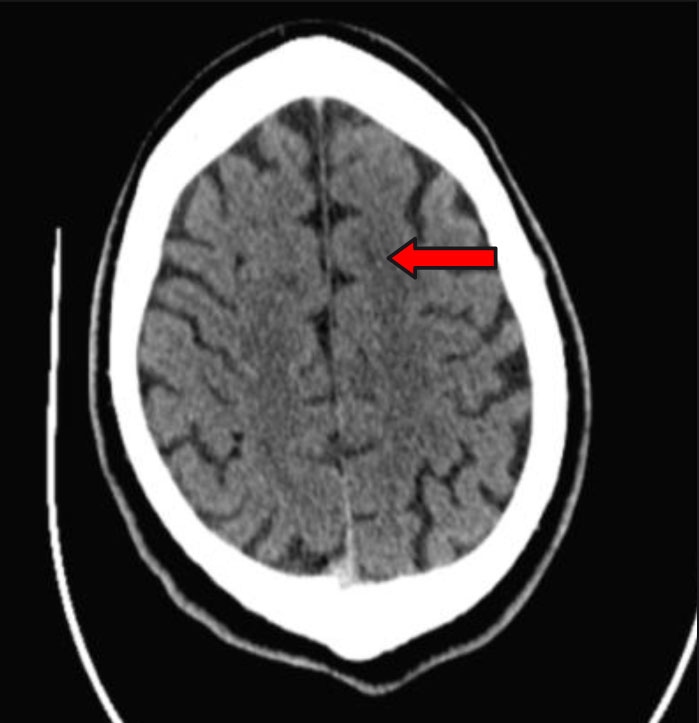

Kontrolní doporučené koagulační odběry nevykazovaly patologii. Následné CT a MR (obr. 3, 4) prokazovaly pouze drobné postischemické změny v povodí ACA vlevo. Primární kardiologické došetření pro suspektní embolizační etiologii neprokázalo zjevnou patologii. Nicméně pacient bude ještě superkonziliárně přešetřen.